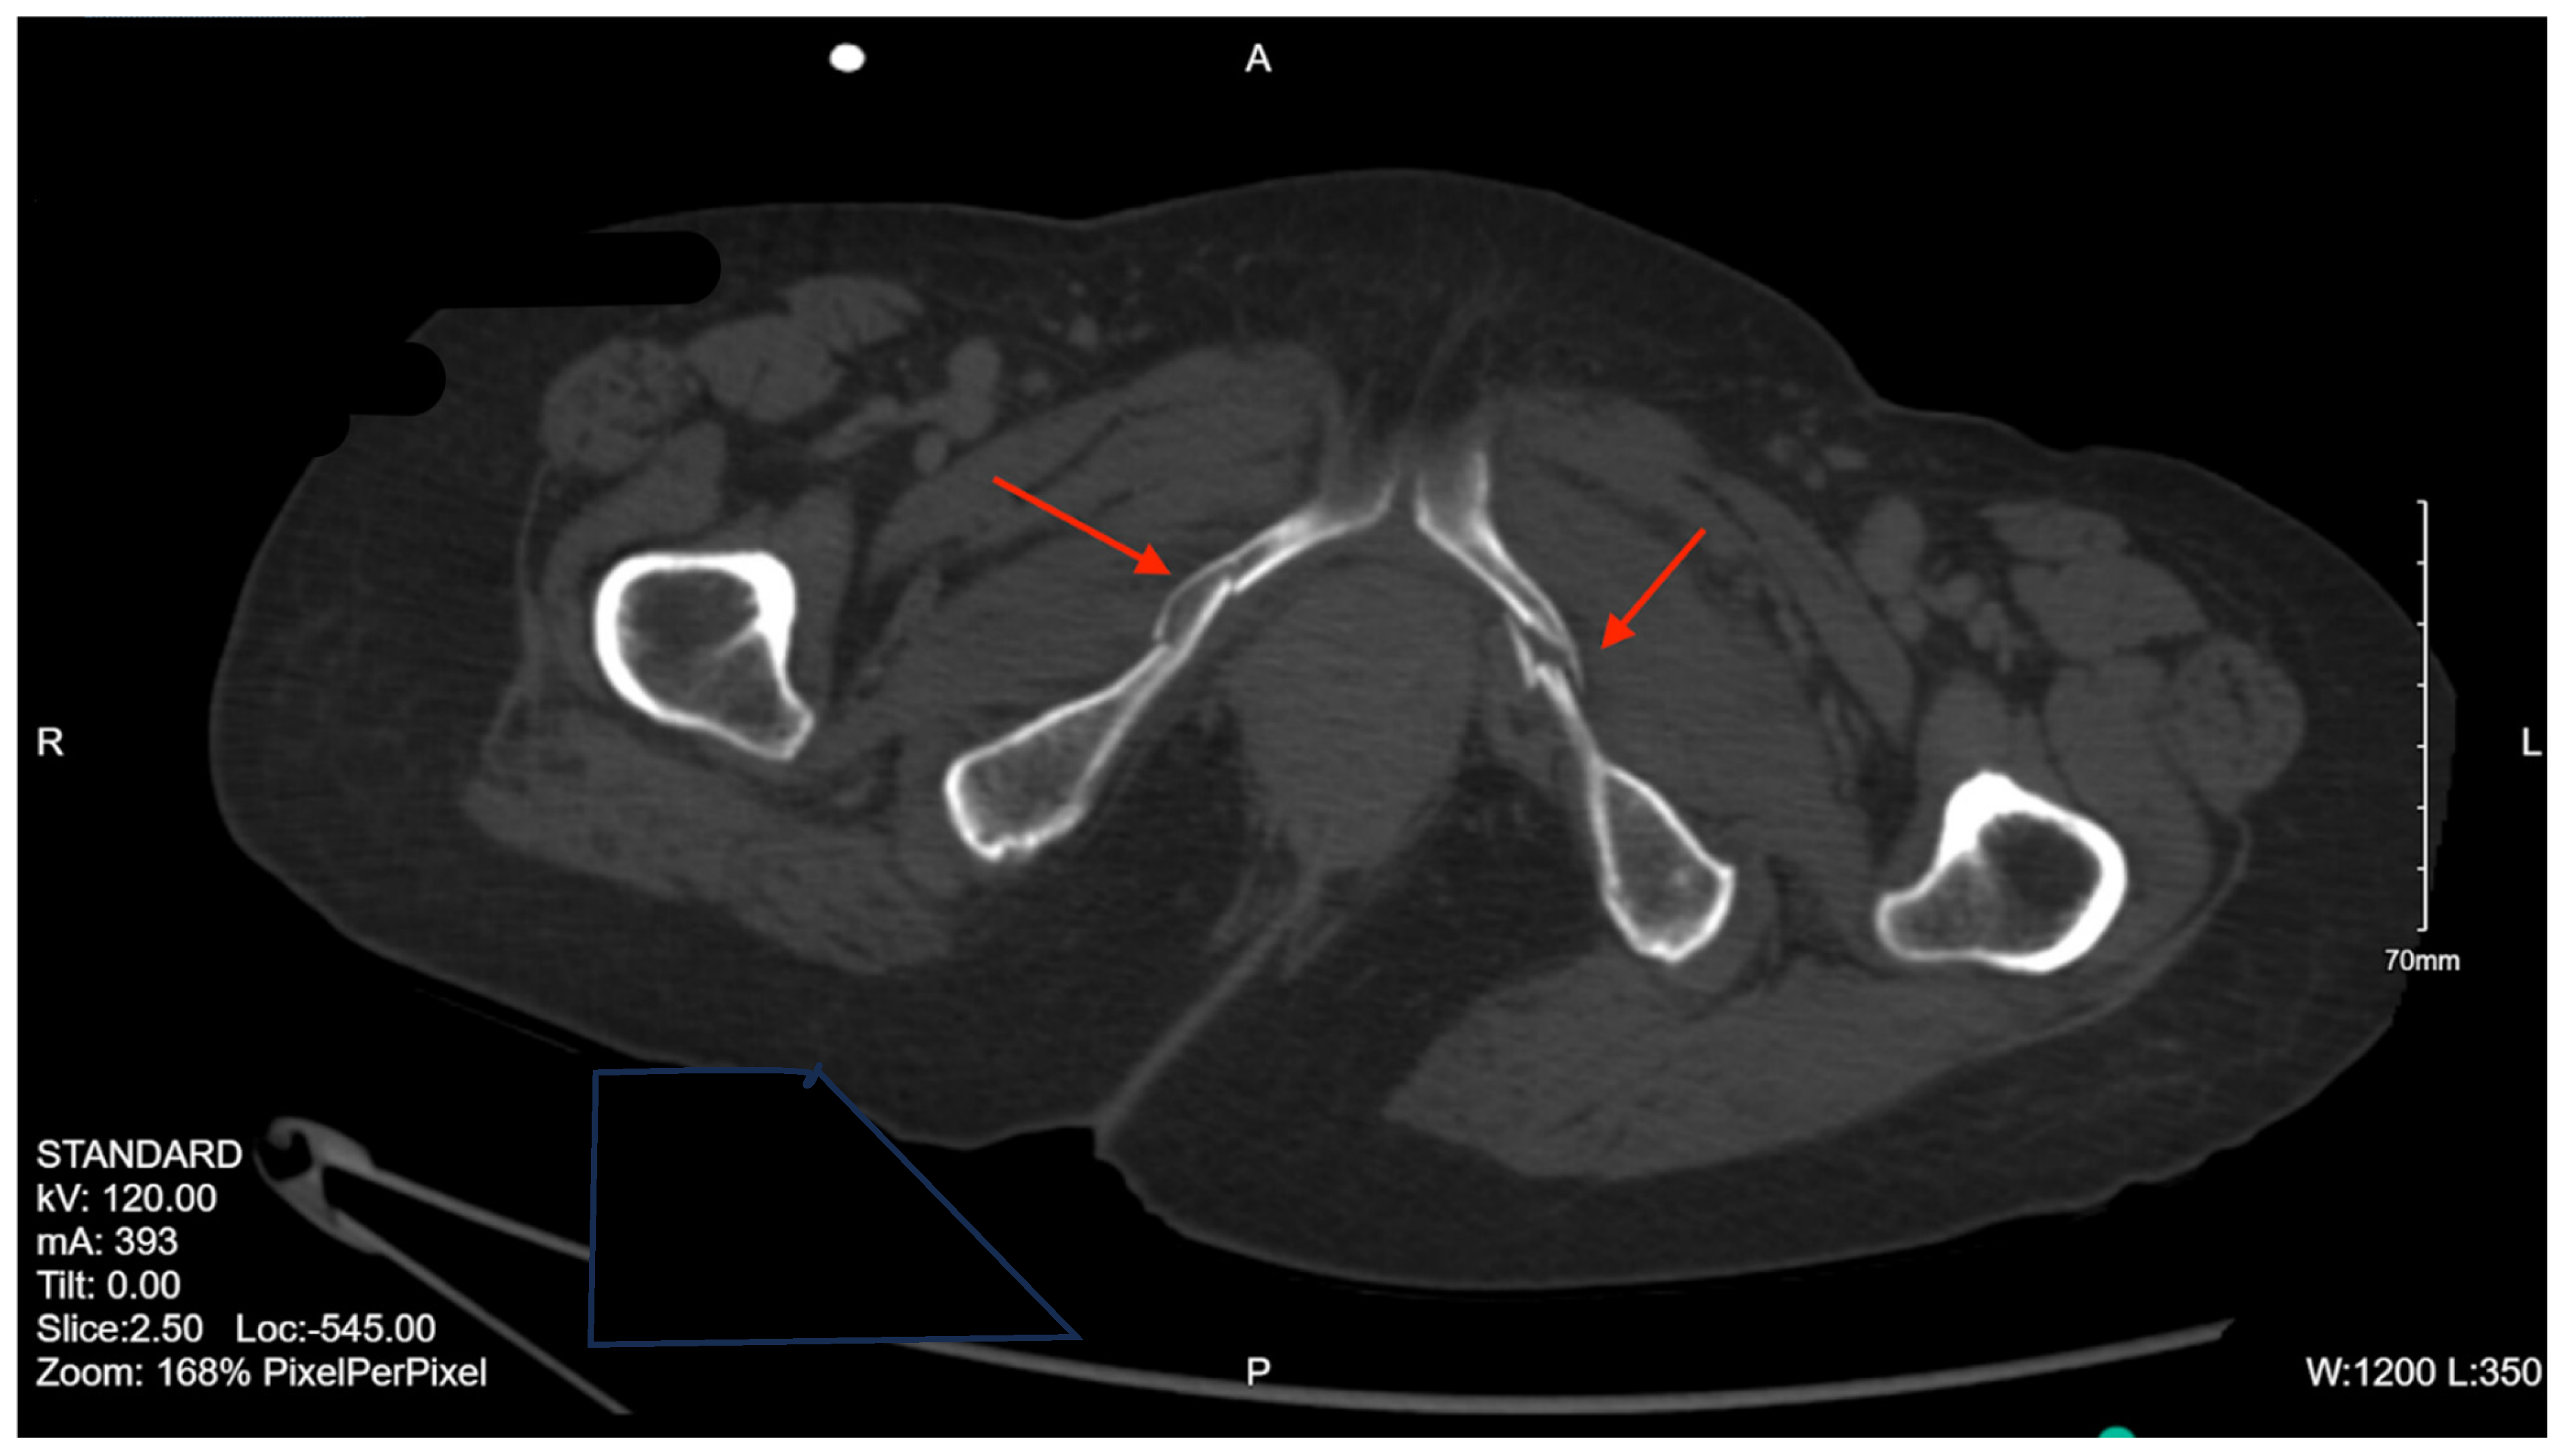

Pelvic imaging performed after surgery showed a transverse S4 fracture (Figure 4). He also had multiple bilateral rib fractures, a left scapula comminuted displaced fracture, multiple cervical, thoracic, and lumbar spine fractures, and facial fractures.

Figure 4. CT abdomen/pelvis images of the described fracture in case 4. Red arrows are used to indicate the location of pelvic fractures for easier identification.